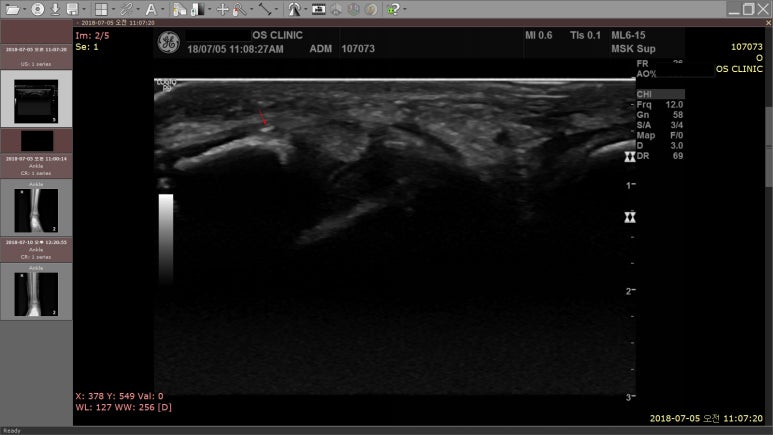

해당 환자의 X-RAY / MSK USG 영상

결과는?

초음파 검사상

견열골절로 진단받고,

통깁스도 하였습니다.